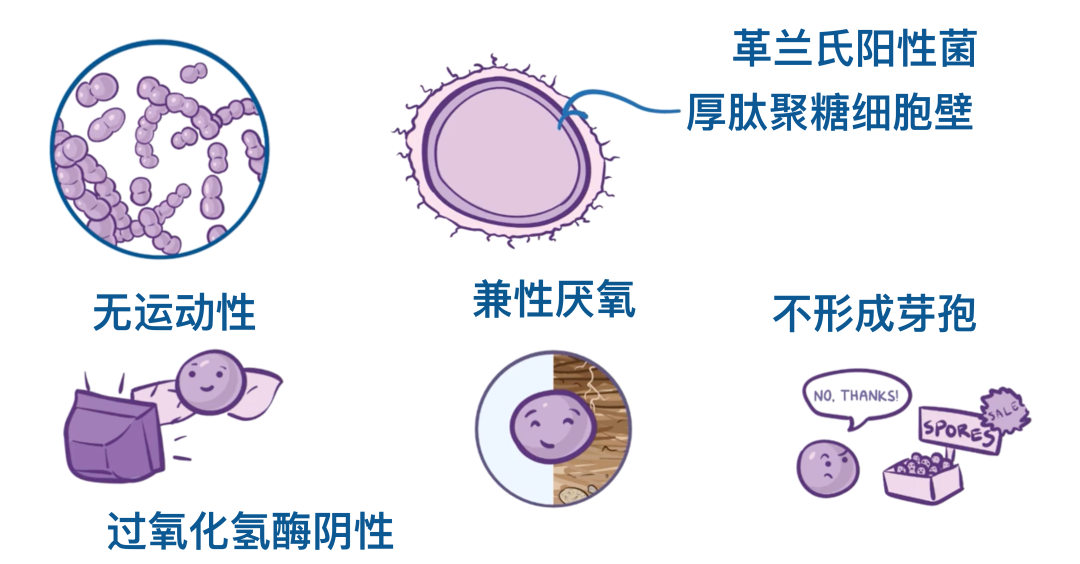

肺炎链球菌具有厚厚的肽聚糖细胞壁,在革兰染色时能吸收紫色染料,因此属于革兰阳性菌。

它们没有运动能力,也不形成孢子,同时属于兼性厌氧菌,也就是说,它们既能在有氧环境下生存,也能在无氧环境下生存。

最后,它们是过氧化氢酶(catalase)阴性菌,意味着它们不能产生一种叫做过氧化氢酶的酶。